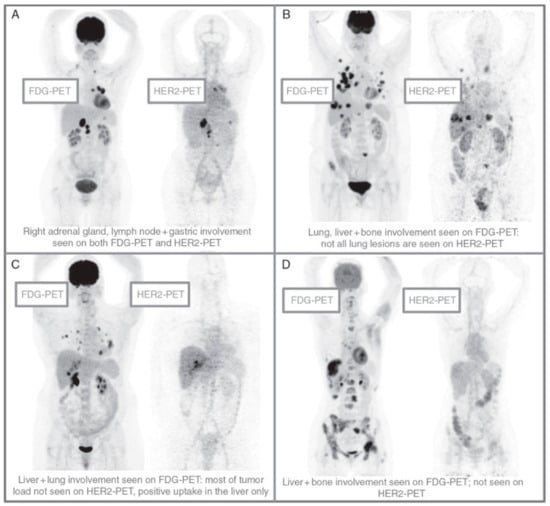

- Gebhart, G.; Lamberts, L.E.; Wimana, Z.; Garcia, C.; Emonts, P.; Ameye, L.; Stroobants, S.; Huizing, M.; Aftimos, P.; Tol, J.; et al. Molecular imaging as a tool to investigate heterogeneity of advanced HER2-positive breast cancer and to predict patient outcome under trastuzumab emtansine (T-DM1): The ZEPHIR trial. Ann. Oncol. 2016, 27, 619–624. [Google Scholar] [CrossRef] [PubMed]